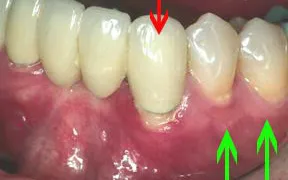

Periodontal Gallery Case 6

The tissue at the gumline of the tooth with the red arrow is not only very red but it is missing what is called the "attached tissue." Without this tissue, bone loss is likely to occur.

Tissue was taken from the roof of the patient's mouth and grafted to the area shown by the green arrows. Compare the image to the right with the image above.